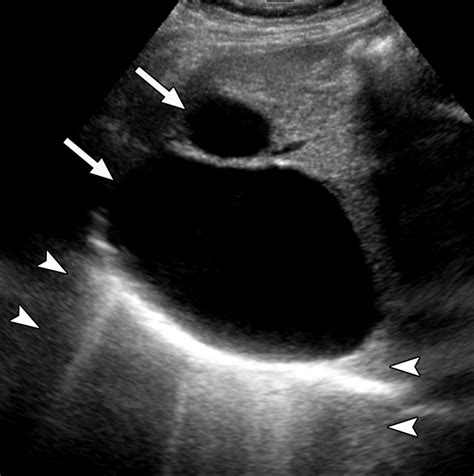

Medical scan of a liver

A cyst on liver, often medically referred to as a hepatic cyst, is a growth that develops within the liver tissue. Think of it as a small, isolated balloon filled with fluid. These are not tumors and are certainly not cancer. They are usually congenital, meaning people are born with them, though they may not be detected until later in life when the liver is imaged for other reasons.